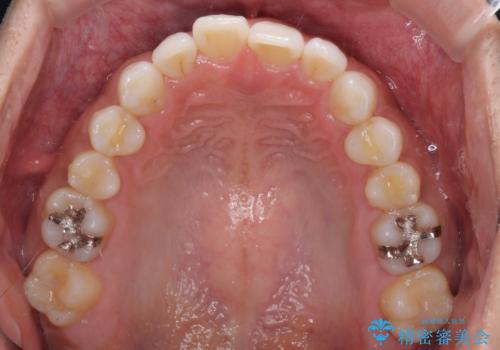

- 上下前歯のデコボコを気にして来院された患者様です。

以前矯正をした後戻りということで、歯列不正はそれほど大きくなかったため、インビザライン・ライトを用いて矯正治療を行うこととしました。

1日22時間以上しっかりと装着してくださったので、半年かからずに治療を終えることができました。